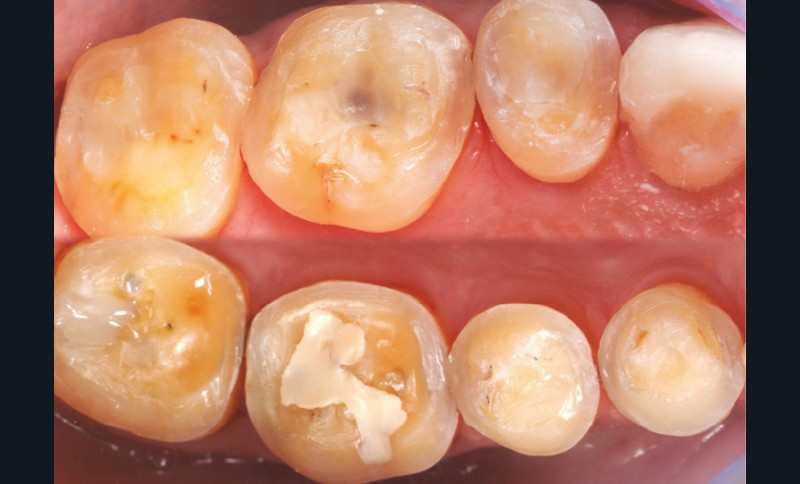

Les overlays (céramique et composite) sont devenus en quelques années un véritable référentiel en termes de restaurations partielles postérieures. Ils sont même les successeurs contemporains de la couronne périphérique dans bon nombre de situations, que ce soit sur dent pulpée présentant un délabrement coronaire important ou sur dent dépulpée pour laquelle le recours au recouvrement de la totalité de la face occlusale est souvent jugé plus indiqué (fig. 1 à 4).

Leurs indications cliniques sont particulièrement fréquentes dans les contextes d’usure érosive pour lesquels il est souvent nécessaire d’augmenter la dimension verticale d’occlusion (DVO) afin d’ouvrir l’espace anatomique antérieur (fig. 5 et 6). Leur dénomination, qui dépend de leur niveau de recouvrement, varie du table top (fig. 7) au veneerlay (recouvrement des faces occlusale et vestibulaire sur de faibles épaisseurs et en intra-amélaire) (fig. 8 et 9). Mais leur indication est aussi posée sur les dents fissurées (« craked tooth syndrome »), dans les cas de dents présentant une fragilisation cuspidienne ou encore en présence d’une dent postérieure en infraposition occlusale.

à ces restaurations correspond aujourd’hui toute une série de nouveaux design postérieurs permettant une ultra-préservation tissulaire et pouvant s’inscrire, en fonction des situations cliniques, dans l’émail (situation idéale), dans la dentine, dans le composite de base intermédiaire, ou un « mix » de ces différents supports (fig. 10 à 13).